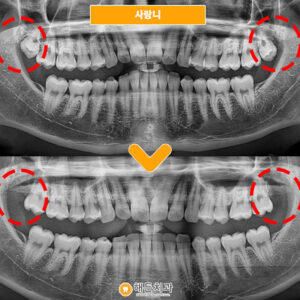

오늘 소개해 드릴 분께서는

오른쪽 두 번째 어금니가

불편하셔서 본.원을 찾아주셨는데요.

치아가 많이 흔들려 식사하실 때

건들리면 통.증도 있고,

잇몸이 붓고 고름으로 인해

냄새가 나서 불편을 겪고 계셨습니다. (ㅠㅠ)

x-ray 사진을 촬영하여 검사해 보니,

차아 주변으로 까맣게 비춰 보이는 부분을

확인할 수 있었는데요,

치아 주변으로 염증도 생기고

뼈도 많이 녹아 있는 상태였습니다.